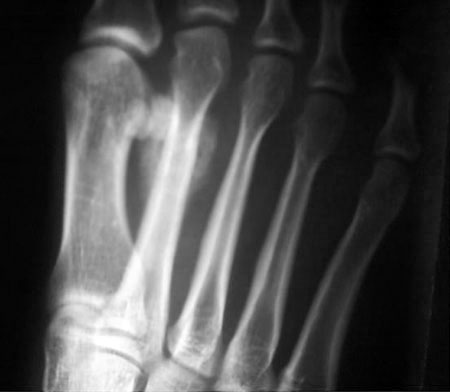

女,28岁,自觉右足局部疼痛近一月,局部肿大,皮温不高,无明确外伤史。

多考虑第2足掌骨疲劳骨折伴修复骨枷或骨化性肌炎。

第2足掌骨行军骨折(即疲劳骨折)

特点:1、好发于第二跖骨骨干远端, 2、骨折后仍能行走, 3、常在骨折后2~3周后就诊, 4、骨折线多不明显,周围有小丘状骨膜新生骨。

28岁的女性,那能走了这么多的路,认为疲劳性骨折可能极小。该病例软组织肿胀明显,结合病史考虑:皮质旁骨肉瘤或骨膜肉瘤。

第2跖骨中、远段交界处内、外侧均可见高密度,但未见骨质破坏,偶考虑疲劳性骨折,女性是否舞蹈爱好者?

支持以上的诊断:特定的好发部位,没有骨质结构的破坏,骨皮质完整,可以和肿瘤相鉴别。建议必要时行ct扫描可能发现隐秘的骨折线。

请见指骨骨折ct矢状面重建图象观察骨折细节:

第一眼的确很像疲劳骨折,但仔细观察发现:病变主要位于骨皮质周围,骨皮质、骨髓腔未见明显改变;疲劳骨折仔细观察一般骨皮质隐约可见透亮线影,透亮线周围骨质增生,形成与骨干垂直的横行致密带状影,一般较规则范围不太大;另外病史非常重要,病人年轻女性,劳累行走可能性不大;所以考虑皮质旁或软组织内病变可能性大。

此例改变为骨周包绕骨密度影,与骨干皮质间隐约示一透亮线影,骨皮质稍增厚。软组织未见明显肿胀。多考虑为表面骨肉瘤,又以皮质旁骨肉瘤可能性大;疲劳骨折后骨痂可能性极小。

第2跖骨中段见骨皮质硬话,骨膜反应.外侧见稍高密度影.

右足第二跖骨远段周围骨痂样密度阴影,边缘清楚,骨皮质边缘欠光滑,未见明显骨折线及硬化带,无明显软组织肿块。符合皮质旁骨肉瘤的影像学表现,该部位虽是疲劳骨折的好发部位,临床除应有明确过度活动史外,影像学应有骨折线或由内骨痂形成的硬化带。